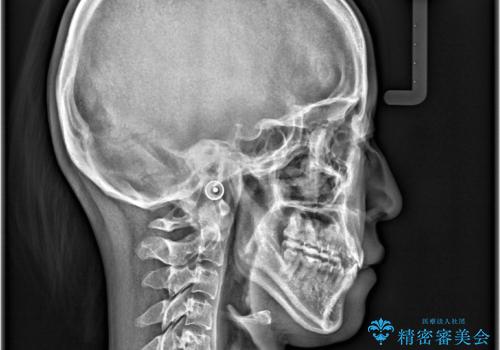

- オープンバイトと八重歯を主訴として来院されました。診査の結果、上顎の骨格的な狭窄と重度の叢生が確認され、非抜歯での改善を希望されたため、MARPE(骨格性急速拡大装置)を用いて上顎の拡大を行う方針としました。その後、インビザラインにて歯列を整え、見た目と噛み合わせの両方を改善する計画としました。

上顎にTAD(矯正用アンカースクリュー)を設置し、MARPEにより骨格レベルで上顎の幅を拡大。数週間の拡大期間を経て十分なスペースを確保したのち、マウスピース型矯正装置(インビザライン)で歯列全体を整えました。八重歯もアーチ内に自然に収まり、非抜歯で審美性と機能性を両立。治療後は「噛み合わせが安定して笑顔に自信が持てるようになった」とご本人にも大変満足していただきました。